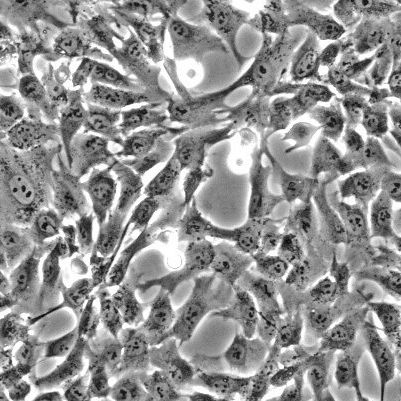

人羊膜间充质基质细胞说明:这个细胞是多能间充质基质细胞,又名间充质干细胞,是特征明确的一类成人干细胞。它们有发育为成熟细胞的潜在能力而产生脂肪、软骨、骨骼和肌肉。这些特性与它们发育中的可塑性共同作用使人们对用间充质干细胞来替换受损组织的潜在能力产生了极大的兴趣。间充质干细胞无血清培养,在转化生长因子作用下会分化成软骨细胞。相反,在有血清、抗坏血酸和地塞米松的作用下会分化成成骨细胞。间充质干细胞有能力更新和分化成多种间充质组织。间充质干细胞由羊膜和绒毛膜中提取得到,表达的CD271控制心肌细胞的特征、并有多种抗血管生成蛋白和抗炎症蛋白。

Sciencell研究实验室的人羊膜间充质干细胞 HAMSC 是从人羊膜组织中分离提取,属第一代冻存,干冰冰冻运输。每管细胞密度5×10^5/ml。人羊膜间充质干细胞经免疫荧光鉴定、和CD73,CD90,CD105的抗体鉴定,以及分化后的脂质染色鉴定。本细胞经检测不含HIV-1、HBV、HCV、支原体、细菌、酵母菌和真菌。采用ScienCell 实验室特制的培养基,可保证此细胞15倍增增殖。